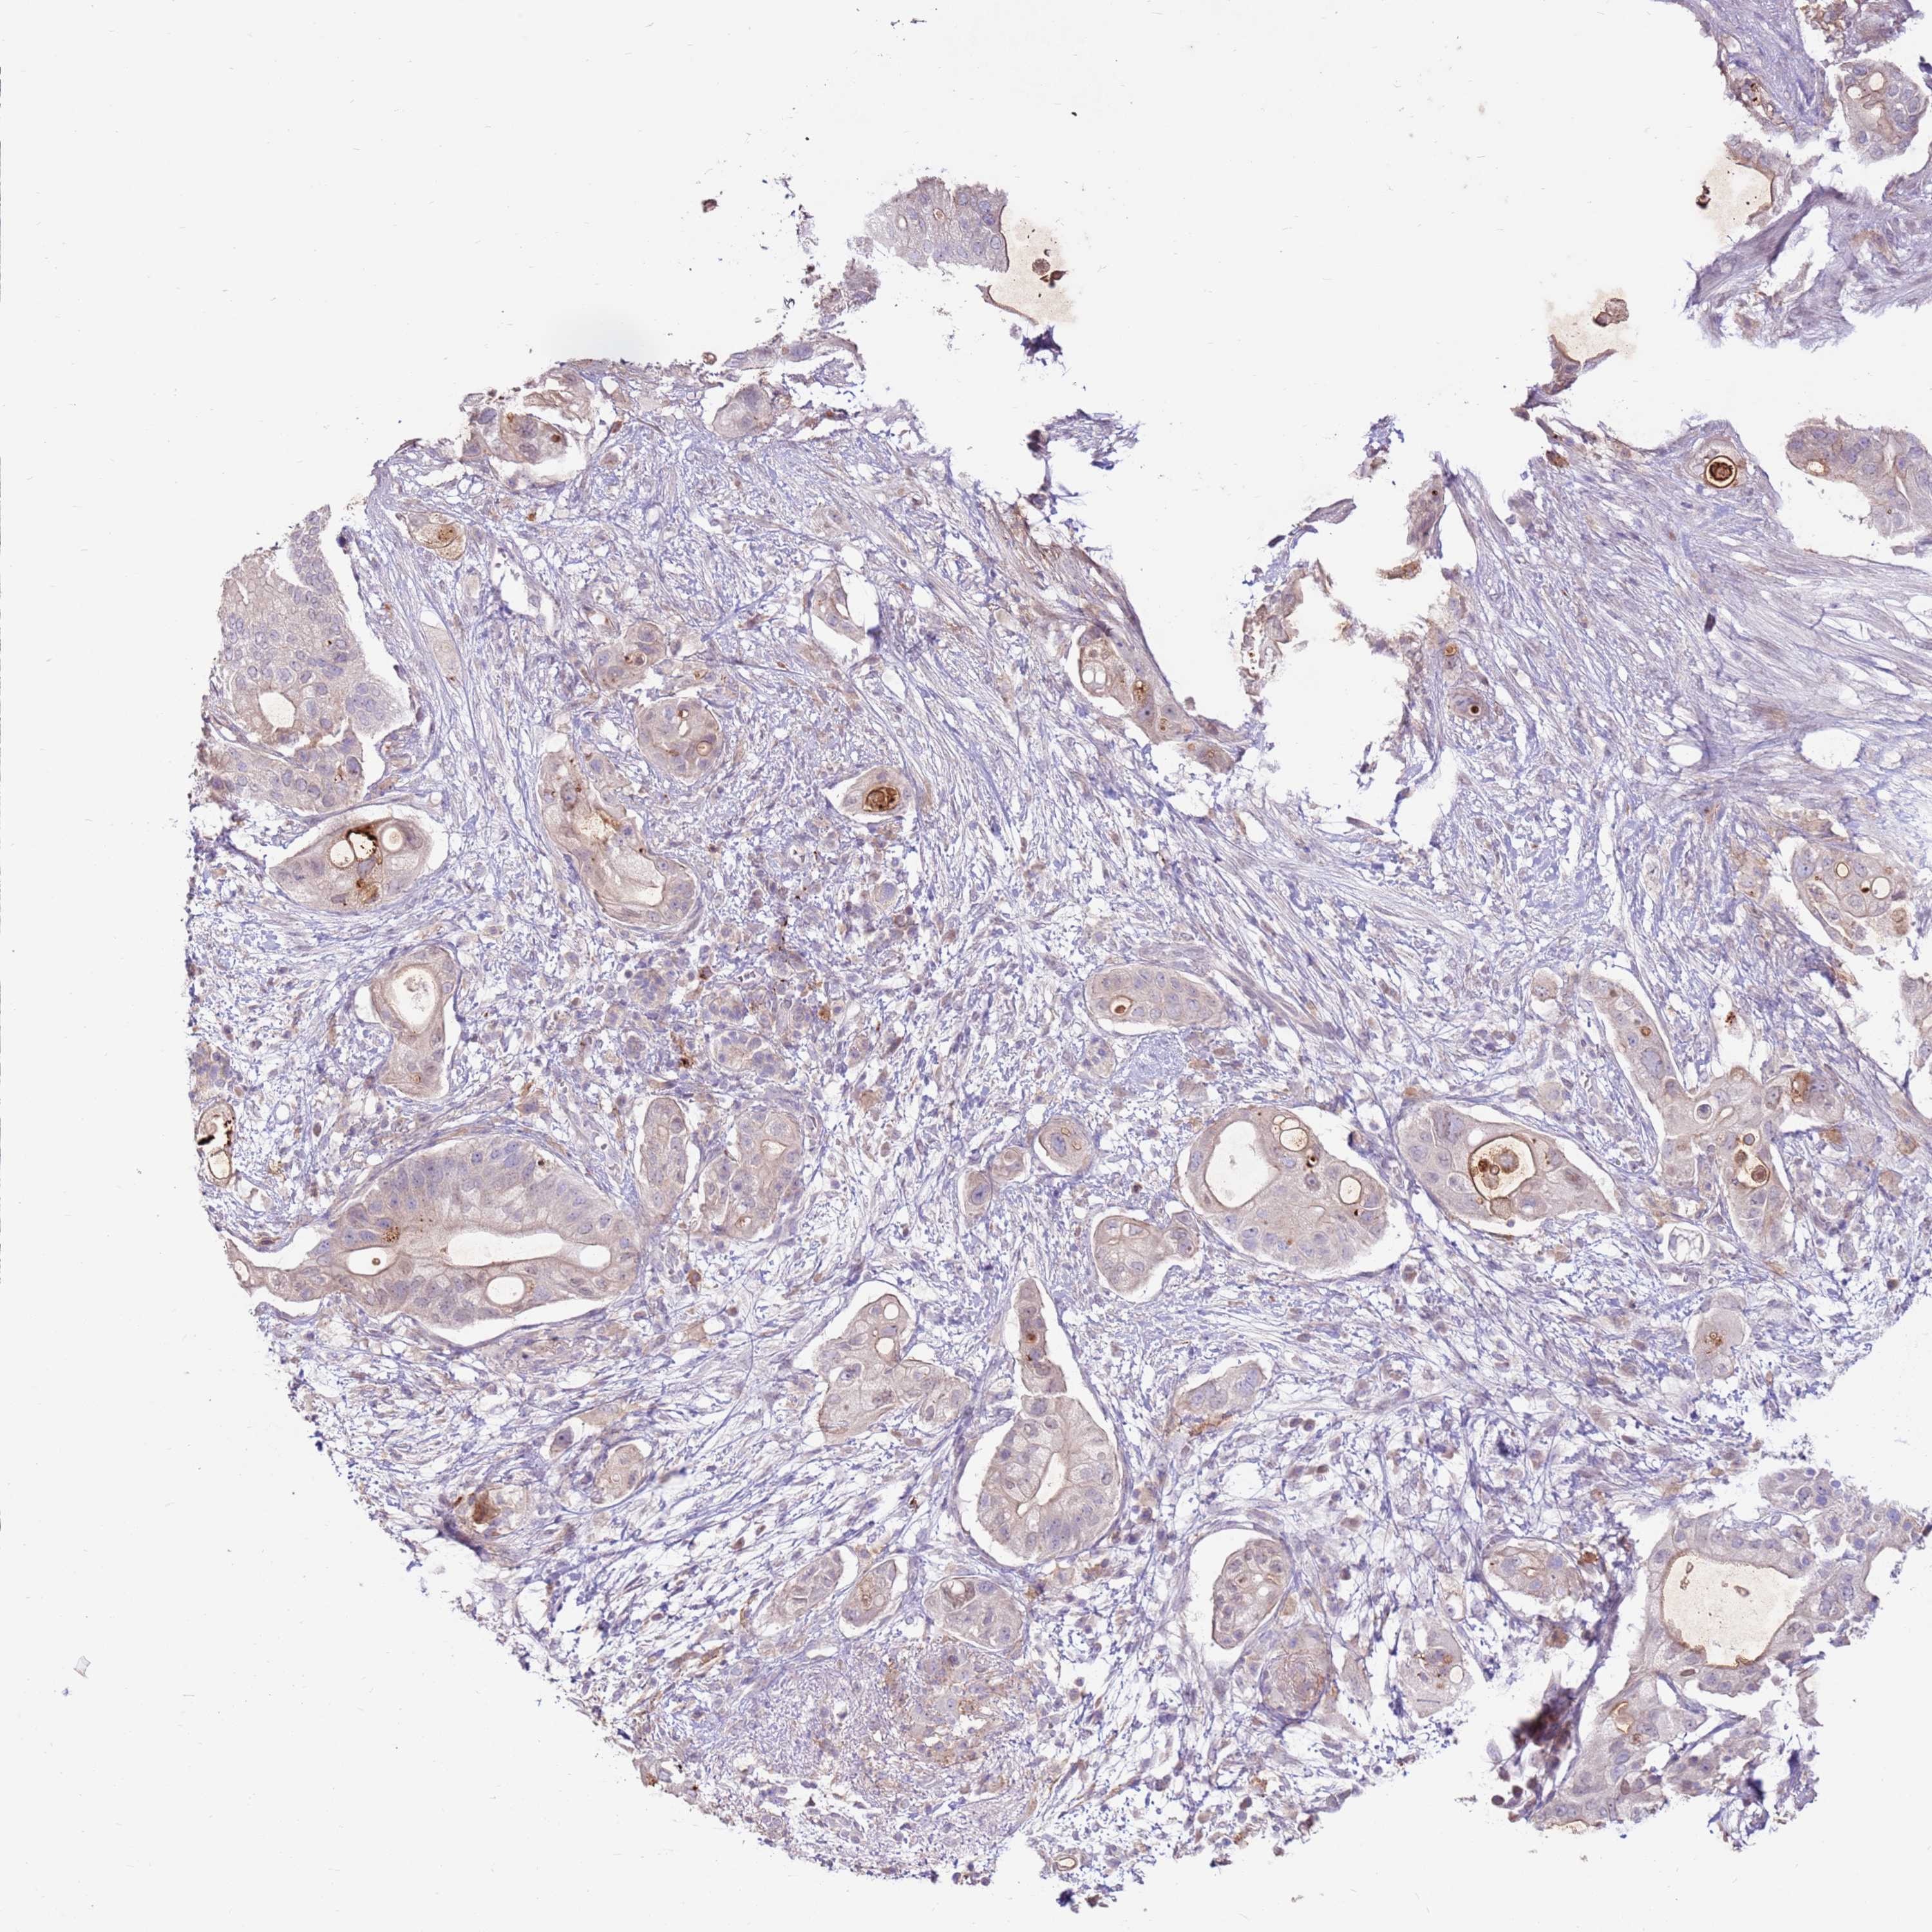

PANCREATIC CANCER - Protein expressioni

A mouse-over function shows sample information and annotation data. Click on an image to view it in a full screen mode. Samples can be filtered based on level of antibody staining by selecting one or several of the following categories: high, medium, low and not detected. The assay and annotation is described here.

Note that samples used for immunohistochemistry by the Human Protein Atlas do not correspond to samples in the TCGA dataset.

Antibody stainingi

Antibody staining in the annotated cell types in the current human tissue is reported as not detected, low, medium, or high, based on conventional immunohistochemistry profiling in selected tissues. This score is based on the combination of the staining intensity and fraction of stained cells.

Each image is clickable and will lead to virtual microscopy that enables deeper exploration of all samples and also displays staining intensity scores, fraction scores and subcellular localization as well as patient and tissue information for each sample.

Antibody HPA042116

Antibody HPA043556

Staining

High

Medium

Low

Not detected

Intensity

Strong

Moderate

Weak

Negative

Quantity

>75%

75%-25%

<25%

None

Location

Nuclear

Cytoplasmic/membranous

Cytoplasmic/membranous,nuclear

Adenocarcinoma, NOS